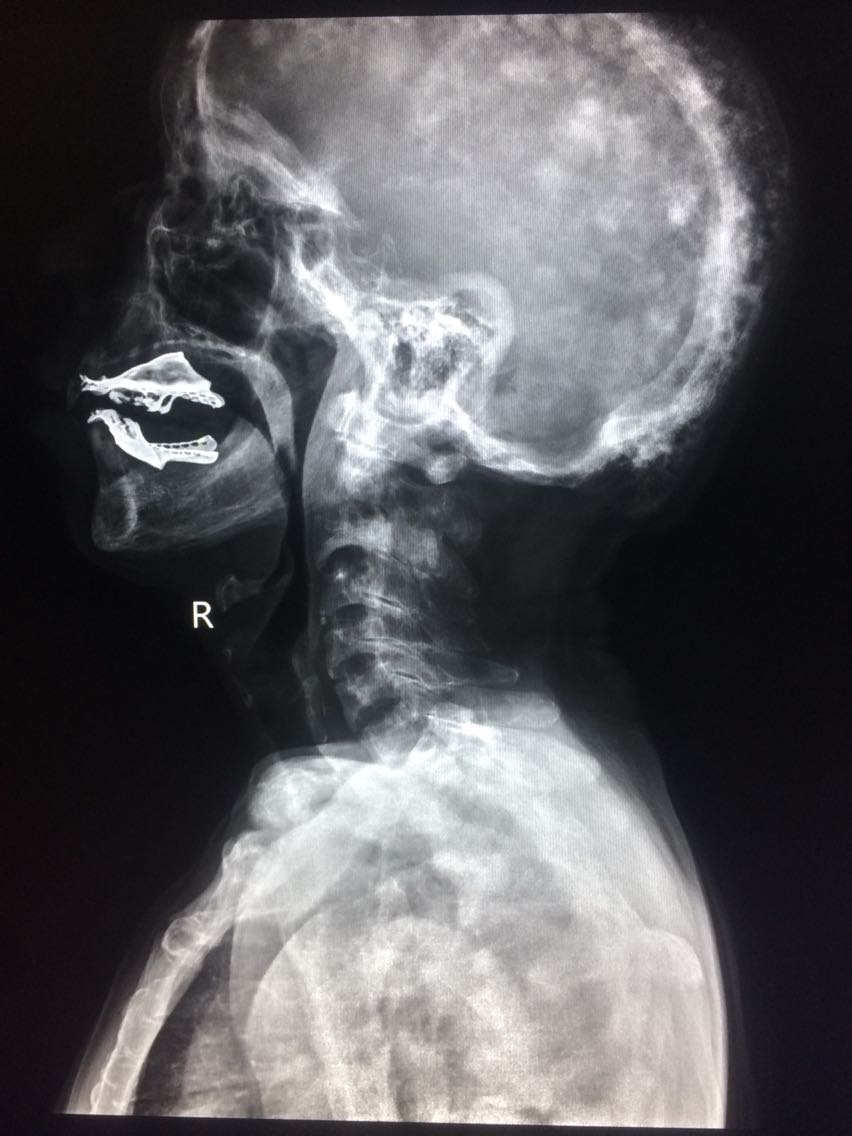

男,65岁 颈部外伤2天。 2天前,在家干农活时,不小心颈部受伤,出现颈部疼痛,活动受限,无恶心,头晕等,遂来诊。 既往无明确病史。

门诊拍片

考虑,佩吉特骨病, 对症治疗。

讨论,该病多见于40岁以上老人,儿童发病少见,具有遗传倾向,大多与病毒感染有关。 无明显症状,并发症较多,对应症状多。 碱性磷酸酶可增高。 棉絮征为颅骨特征性的影像征像。 遂访,注意身体其他部位有没有骨质改变。